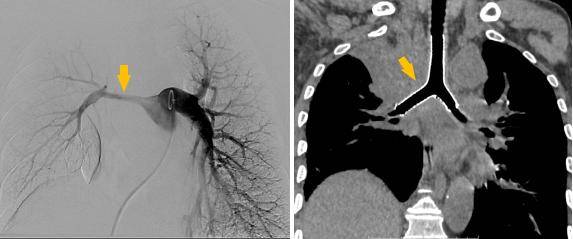

同期置入支架后狭窄明显改善

重生:从呼吸困难到畅快呼吸